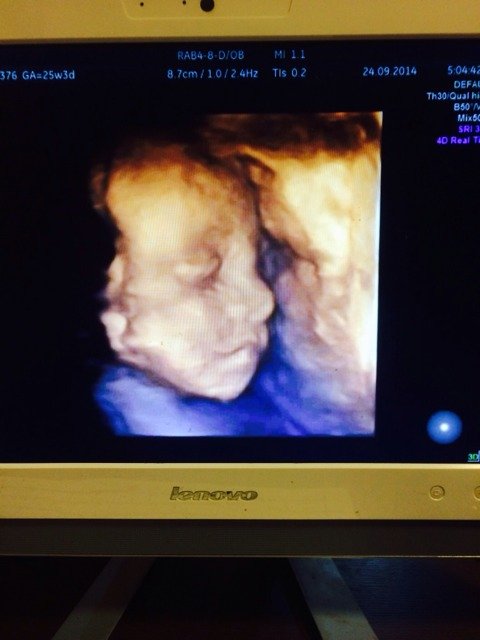

我宝宝的四维照片,22周时候拍的,可爱不? 点击展开 小安/ 2014-11-02 04:29 为您推荐: 其他回答 孕妇在早孕时期非常容易流产,必须特别注意,不应搬运重物或激烈运动,外出次数也就尽可能减少。不可过度劳累,多休息,睡眠要充足,并应控制性生活。在感到特别疲劳时不要洗澡,而要及早卧床休息。 焰火810 2014-11-02 19:27 相关问题 我宝宝的四维照片,22周时候拍的 22周只做胎心给做吗?我想等半月去做四维呢? 22周+5天做四维行吗孩子相貌长好了吗